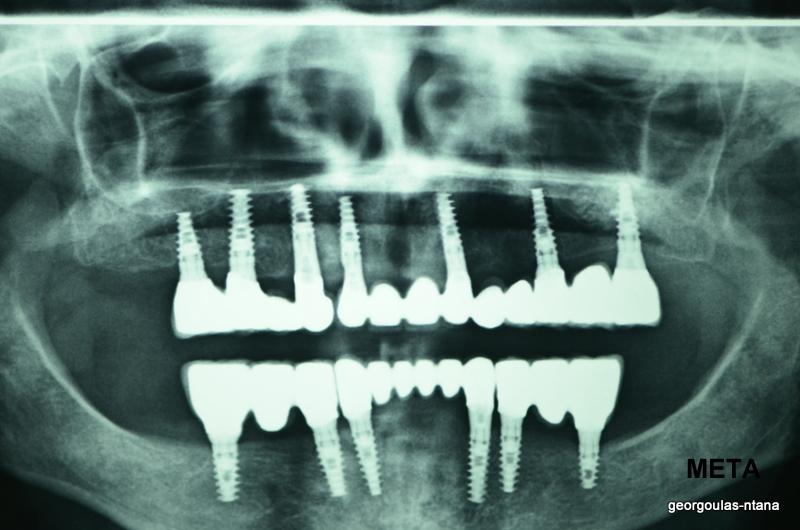

ΟΛΙΚΗ ΑΠΟΚΑΤΑΣΤΑΣΗ ΑΝΩ Κ ΚΑΤΩ ΓΝΑΘΟΥ ΜΕ ΕΜΦΥΤΕΥΜΑΤΑ, ΑΜΕΣΗ ΦΟΡΤΙΣΗ Κ ΑΝΟΙΚΤΗ ΑΝΥΨΩΣΗ ΙΓΜΟΡΕΙΟΥ